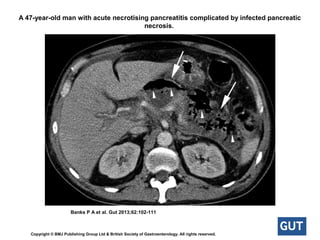

Infected pancreatic necrosisInfected pancreatic necrosis

• Necrosis is variable, may remain solid or liquefy, remain sterile or

become infected, persist, or disappear over time.

• occurs > the first week.

• Infected pancreatic necrosis is important because of the need for

antibiotic treatment and likely active intervention.

• The presence of infection - extraluminal gas in the pancreatic and/or

peripancreatic tissues on CECT or PFNA is positive for bacteria and/or

fungi on Gram stain and culture.

• There may be suppuration (pus) associated with the infected

pancreatic necrosis, leading to liquefaction – abscess

A 47-year-old man with acute necrotising pancreatitis complicated by infected pancreatic

necrosis.

Banks P A et al. Gut 2013;62:102-111

Copyright © BMJ Publishing Group Ltd & British Society of Gastroenterology. All rights reserved.